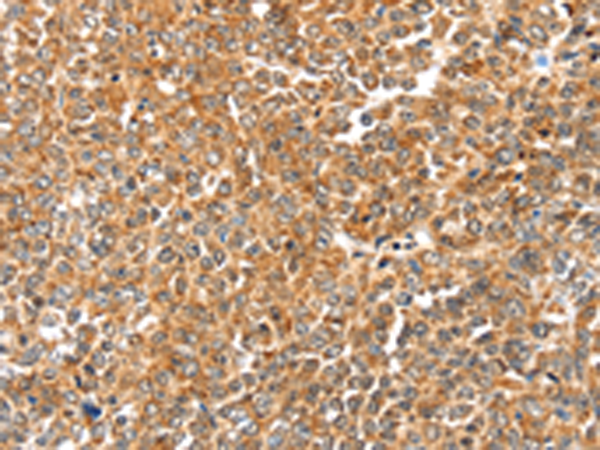

分类: 科研抗体货号: P05079别名: RNO; PAN6; RNO2; FCAS2; NALP12; PYPAF7; CLR19.3应用: IHC反应种属: Human, Mouse